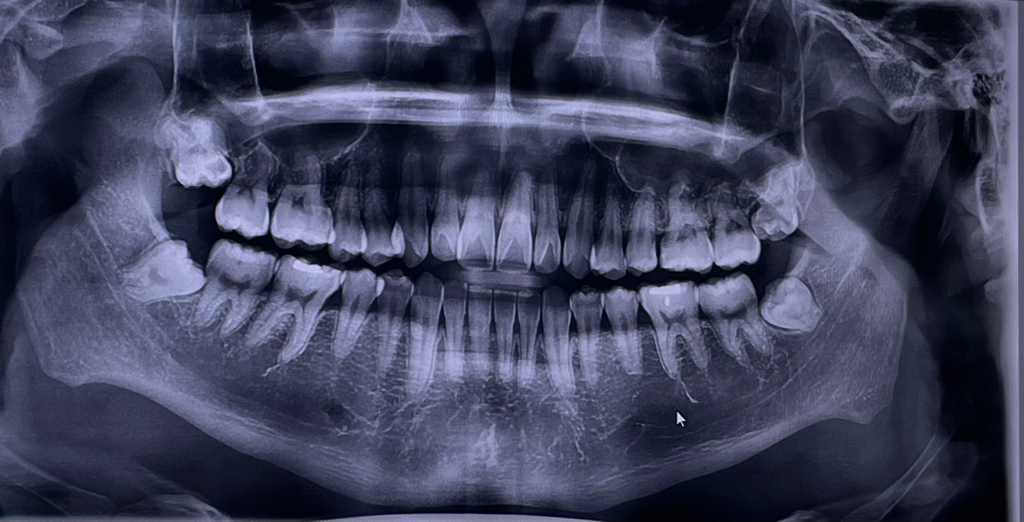

사랑니 위치는 사진대로이고 좌측 상단만 살짝 나있습니다 나머진 안났구요 통증은 없습니다 위치가 꼭 뽑아아하는 사랑니위치일까요?

• 1번 째 사진